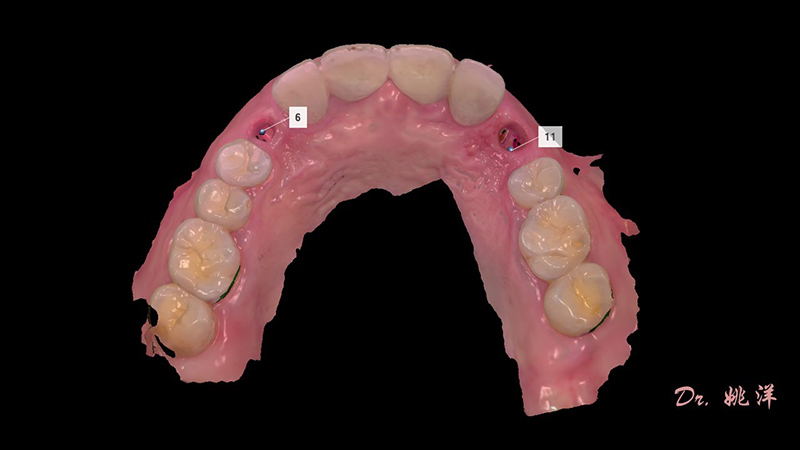

檢查:22烤瓷牙表面崩瓷,13、23、24缺失

種植后數(shù)字化取模,前牙美學(xué)間隙精確分配

從最終修復(fù)效果可以看出:23,24間隙不足修復(fù)兩顆,修復(fù)為1顆牙。因?yàn)榻?jīng)過(guò)數(shù)字化設(shè)計(jì)和精確導(dǎo)航植入,修復(fù)體齦緣協(xié)調(diào)自然